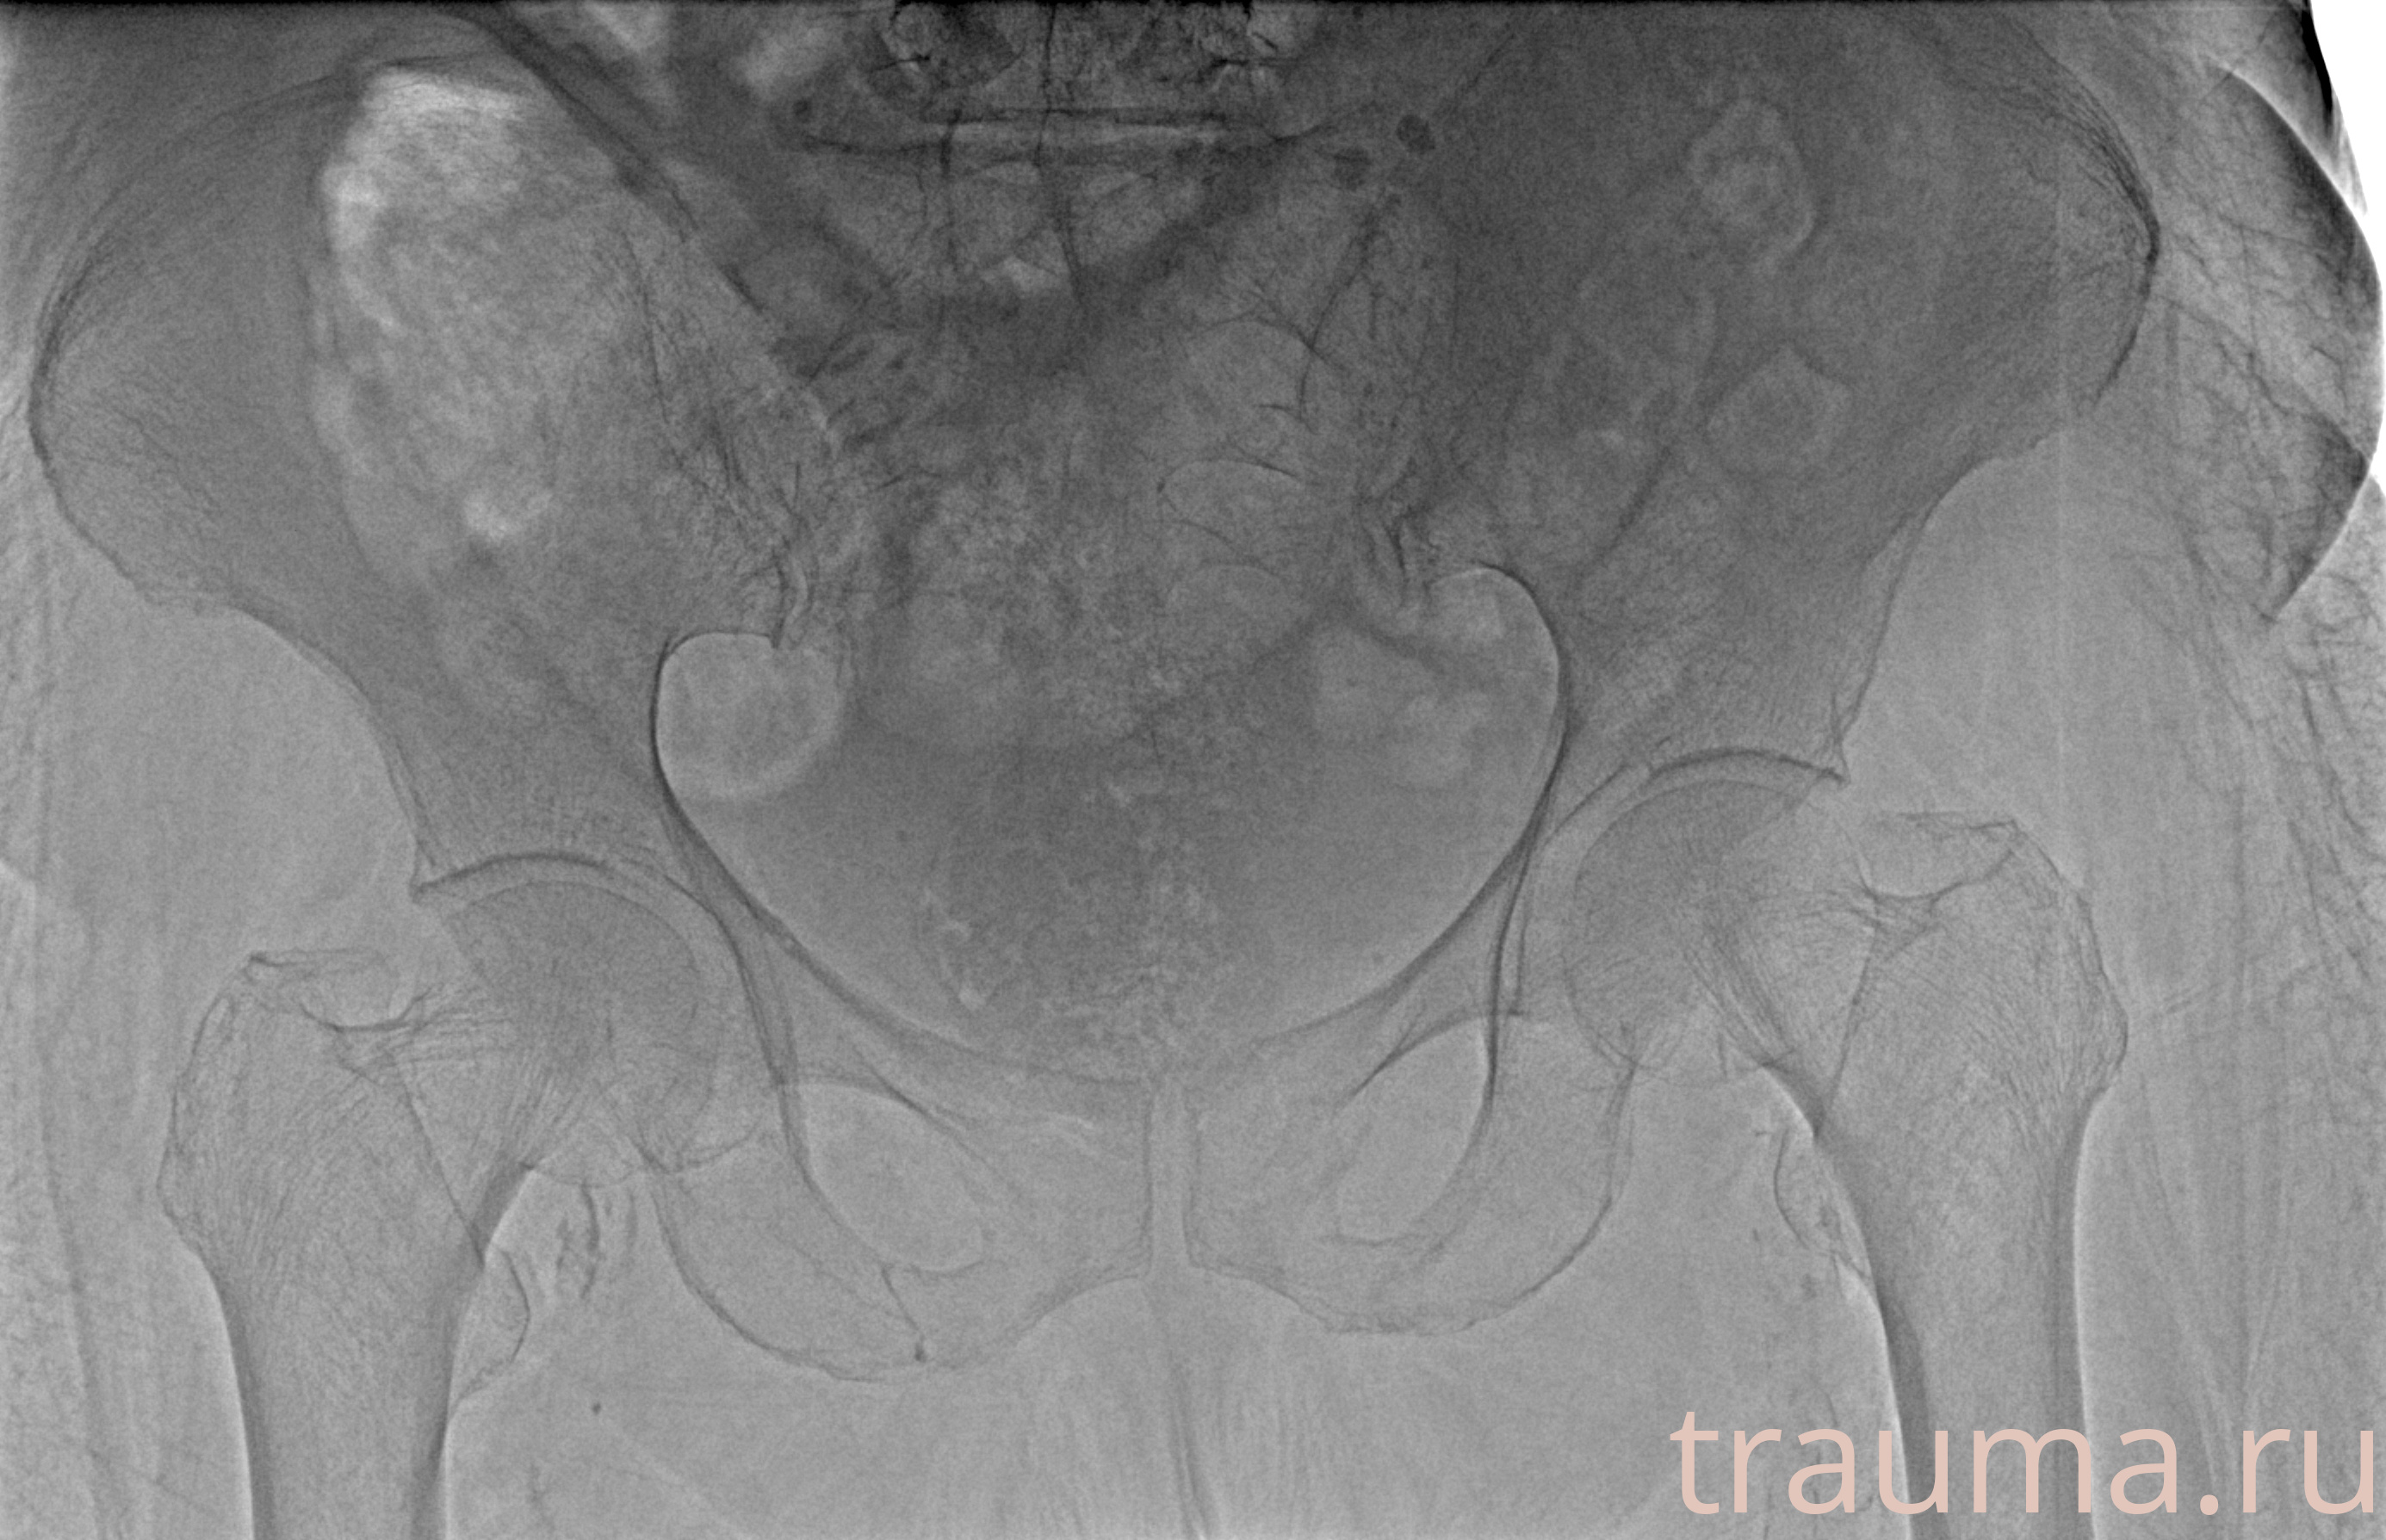

Рентгенограммы

Рентген на дому: по вашему адресу приезжает врач-рентгенолог, травматолог-ортопед с мобильным рентгеновским аппаратом, проводит диагностику травмы или заболевания, делает необходимые рентгенограммы, дает рекомендации по дальнейшему лечению. Получить качественные снимки в домашних условиях возможно благодаря уникальной методике, разработанной МосРентген Центром для института  Склифосовского